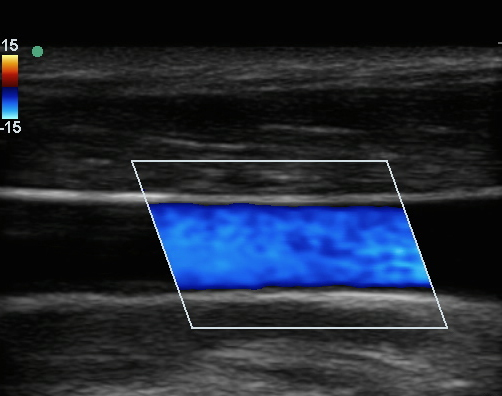

贵要静脉彩色 1 图像